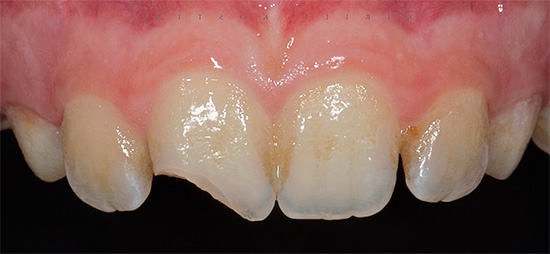

Domanda: Perché i canali sono più facili da trattare con la pulpite dei denti anteriori superiori?

Quando compaiono i sintomi della pulpite del dente anteriore, la maggior parte delle persone si rivolge al dentista per chiedere aiuto. Poiché tutti i denti anteriori superiori dal canino al canino hanno un solo canale, molto spesso largo, in quasi il 100% dei casi vi sono rischi di complicanze durante e dopo il trattamento della pulpite dentale minimizzato. Di solito, il trattamento canalare richiede 2 volte meno tempo del trattamento intracanalale dei denti posteriori (hanno molte radici e la percentuale di anatomia canalare complessa è alta).